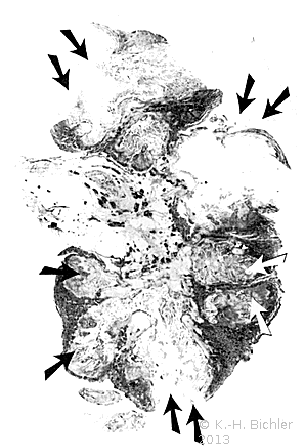

Sie tritt zumeist bei Patienten mit Diabetes Mellitus bzw. bei Harnwegsobstruktionen auf (Komplizierte Pyelonephritis). Dabei können eine oder alle Papillen befallen sein. Histologisch findet sich eine koagolative Infarktnekrose, d.h. die Umrisse von befallenen Tubuli sind erhalten. Leukozytäre Reaktionen finden sich an den Rändern der Nekrosebezirke Literatur:Robbins: "Pathologic Basis of Disease", Saunders Philadelphia, 1999.